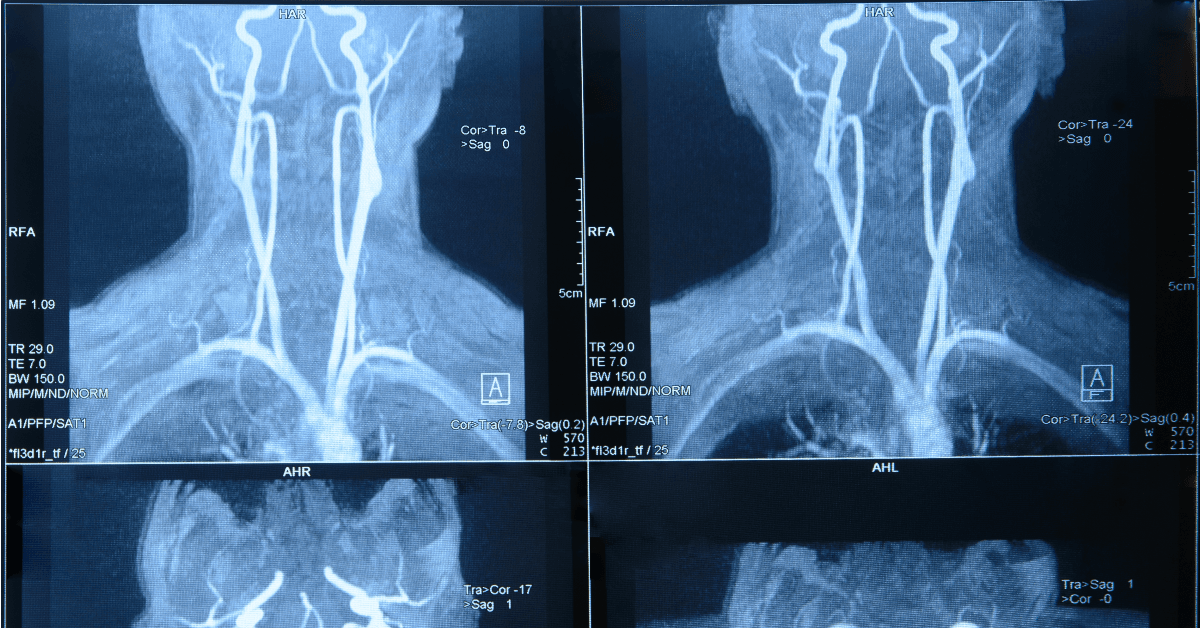

Introdução A angiografia é um procedimento médico amplamente utilizado para visualizar vasos sanguíneos e diagnosticar condições vasculares. Entretanto, pacientes que fazem uso de anticoagulantes, como a varfarina, precisam de cuidados especiais antes de se submeterem a esse exame. A combinação…